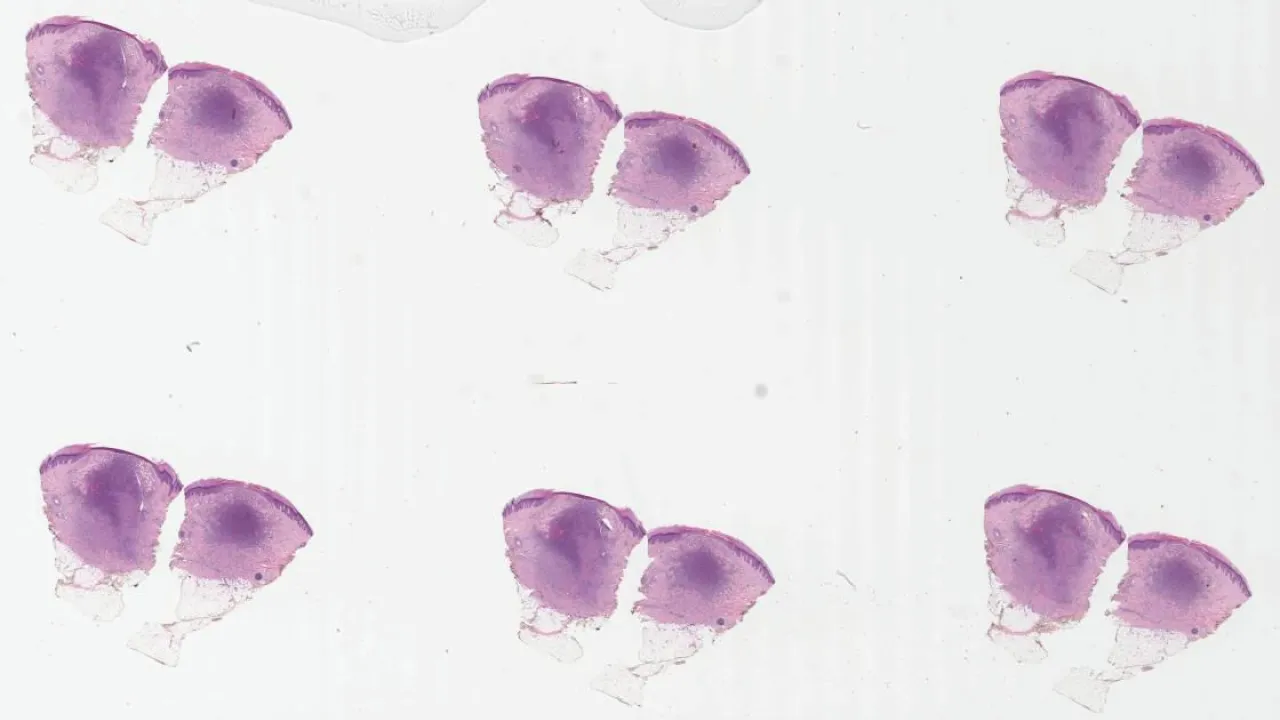

Skin, Pilomatrixoma